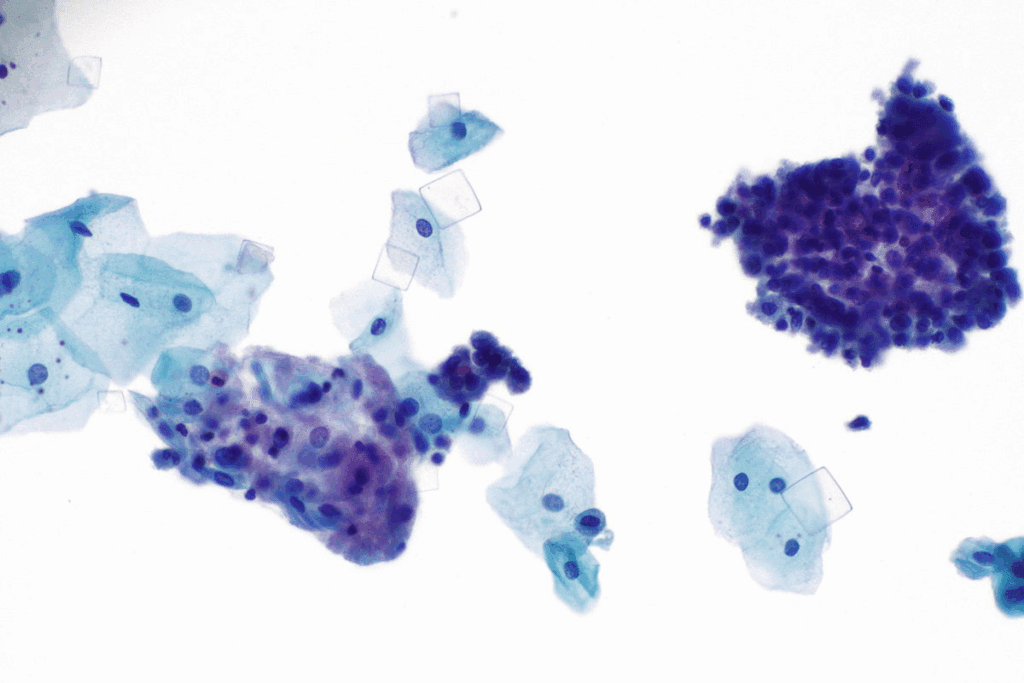

Microscopic Appearance

When seen under a microscope, amorphous urate crystals look like small, yellow to black specks. This speckled look is a big clue for spotting them. The shape of urate crystals can change, but their unique look is always a giveaway.

Color and Structure

The color of urate crystals can be yellow or black, depending on several things. They have a granulated shape, which is easy to see with a microscope. This granulated shape is what makes urate crystals stand out from others.

Amorphous urate crystals are common in urine samples. They look like small, yellow to black granules under a microscope. Their amorphous shape makes them easy to spot.